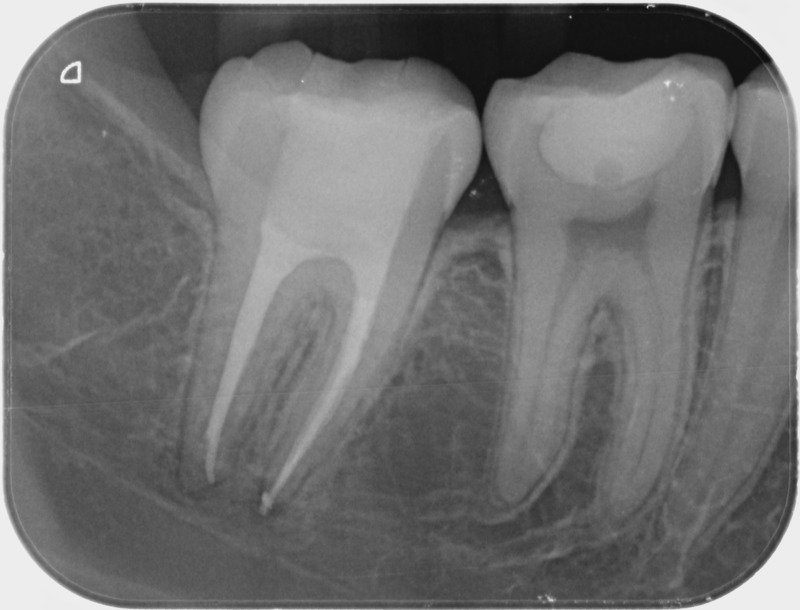

Avant

• Traitement endodontique : Sous anesthésie locale et à travers la protection d’un champ opératoire nous accédons à la pulpe de la dent à soigner, puis aux canaux de ses racines que nous devons désinfecter. Ce soin nécessite l’élimination complète de la source de contamination (souvent la carie) parfois sous une ancienne reconstitution ou une couronne qu’il faut alors retirer. Une fois le nettoyage et la mise en forme des canaux réalisés, nous les obturons de façon hermétique avec un ciment et un matériau thermoplastique appelé Gutta Percha. Ceci afin d’empêcher une nouvelle prolifération bactérienne et d’assurer le maintien de la dent dans ses structures de soutien (ligament parodontal et os alvéolaire). L’ouverture effectuée au centre de la dent sera d’abord refermée avec un pansement provisoire avant d’envisager ensemble la reconstitution d’usage : un composite, un inlay-onlay ou une couronne.